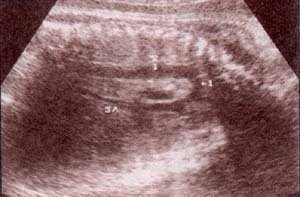

| fig 30. -(a). septum i-v. septum i-v. 32 semana | fig. 30.– (b). septum i-v íntegro entre las flechas. 35 semanas |

| fig 31. válvulas a-v. válvula mitral (1). válvula tricúspide (2). | fig. 32. válvulas a-v.válvula mitral (1). válvula tricúspide (2). |